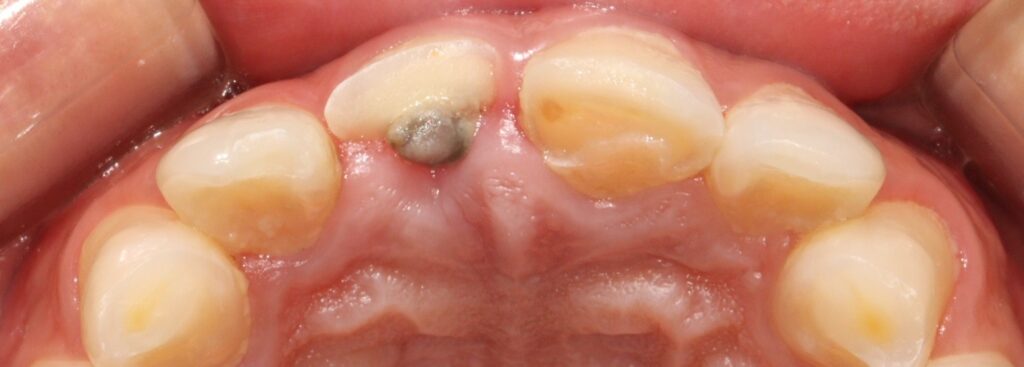

예시 사진을 보면

앞니의 2/3이상이 부러져 사라진 것을

확인할 수 있는데요.

2025.02.12

그로 인해 11번의 경우

자연치 내부 치수가 드러난 것을

볼 수 있으며,

21번은

치수가 드러나지 않았지만

많은 양의 치질이 사라져 있습니다.